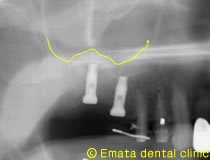

After

インプラントが2本はいりました。上顎洞(黄色い線)があがったのがわかりますね。

サイナスリフト(ラテラルウインドウテクニックによる上顎洞底挙上術)にて同時インプラント埋入しました。